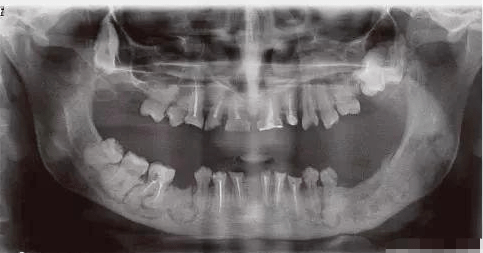

他是一个年轻的父亲,还患有罕见病——很大牙骨质瘤,全世界患此病症的,不到10人。

肿瘤长在他的上下颌骨处,反复引发牙骨化脓病变,帆叶网,最后导致颌骨的肿胀、面部严重畸形。

经过多次手术,李永学只剩下一颗臼齿,就是我们俗称的大牙。他也因此被称为“臼齿爸爸”。

出生6个月后,女儿也被诊断为很大牙骨质瘤症,肿瘤大到嘴巴无法闭合,脸部严重畸形。